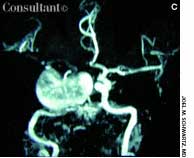

A 56-year-old man who had hematuria for 2 weeks underwent ultrasonography. This disclosed a well-circumscribed cyst in the lower pole of the left kidney and echogenic foci in the upper pole of the right kidney, without any evidence of posterior shadowing. A hyperechoic, well-circumscribed, circular focus was also seen in the right lobe of the liver. Abdominal CT confirmed the presence of a left renal cyst and revealed a 4.7-cm hypodense lesion in the right lobe of the liver, which suggested hemangioma.